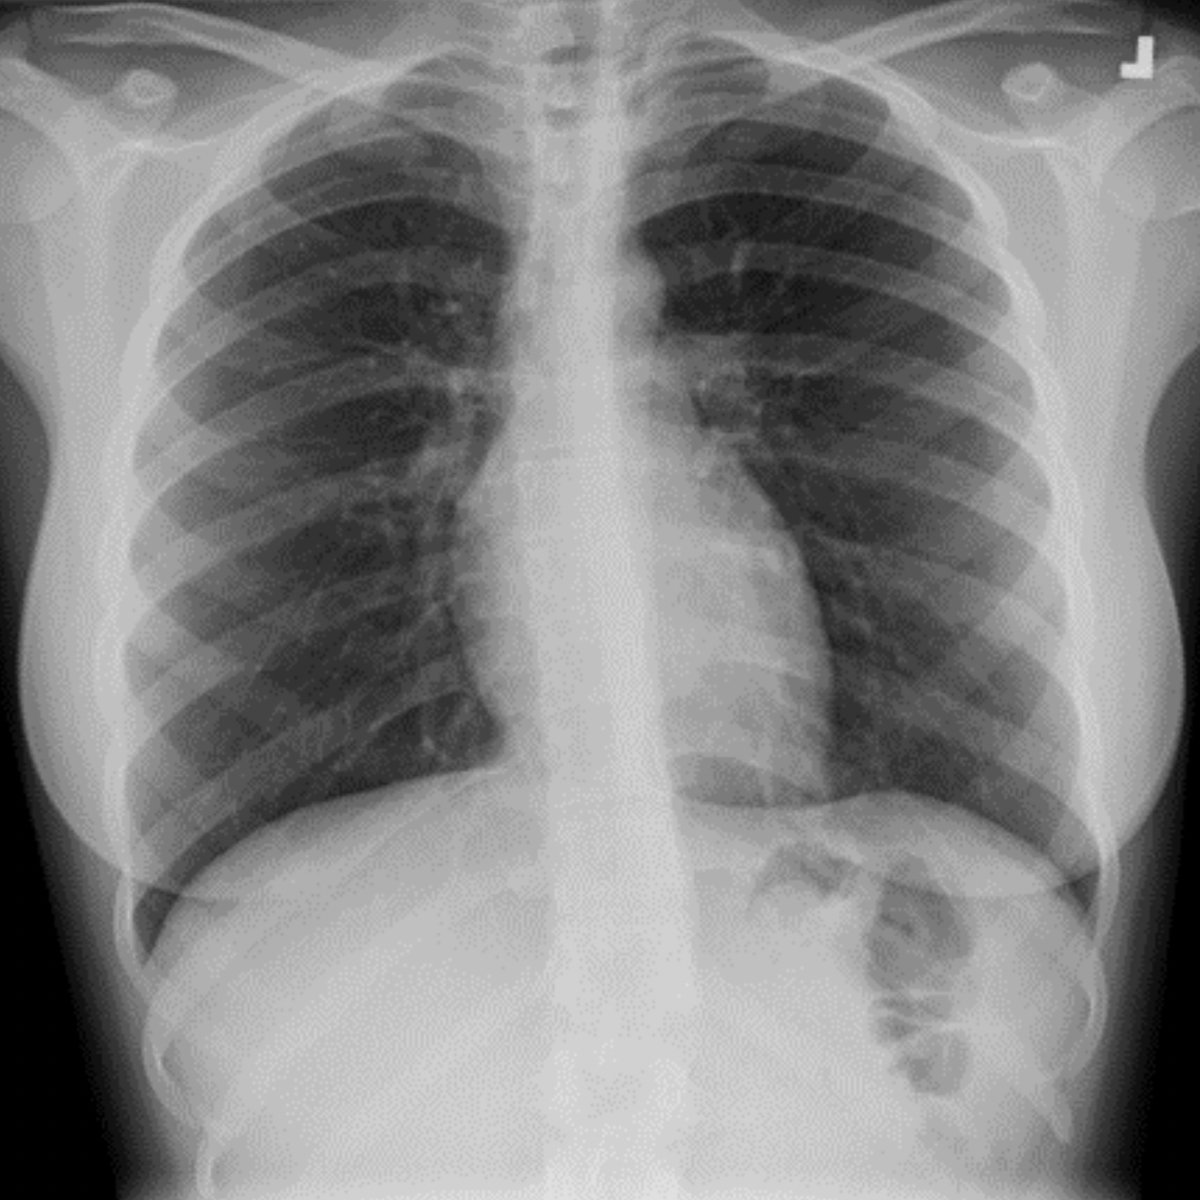

Have you seen our November 2022 Thoracic Case of the Month? 77 yo F w/ 40-year smoking history, presents with worsening shortness of breath and left rib pain… submitted by @AWSongMD & Joseph Lowry MD from Staten Island University Hospital. thoracicrad.org/assets/index/2…